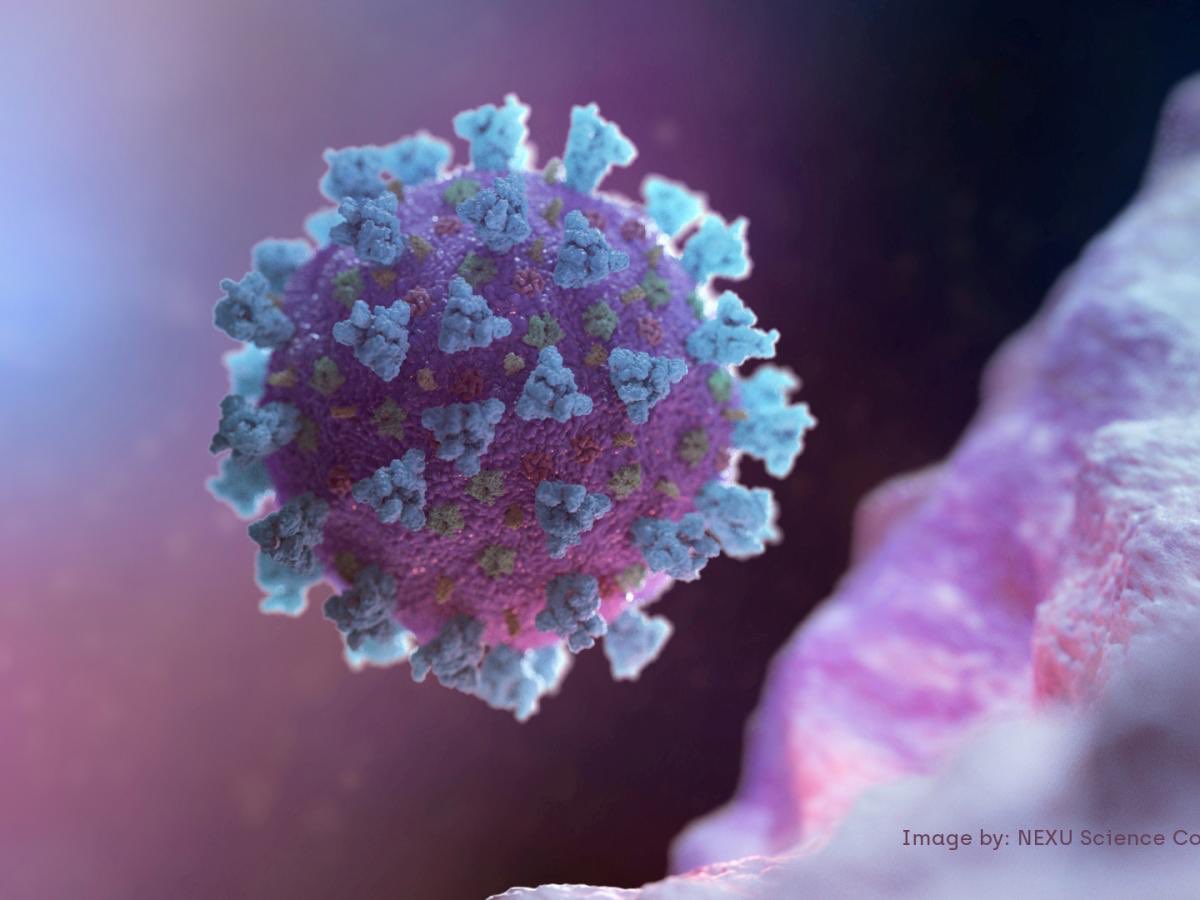

#ثريد جديد : تاريخ الفيروسات في كوكب الأرض، أول فيروس قبل 3500 سنة وتسجل على الورق قديماً وكانوا يعتبرونه مرض قديم ويسبب رشح في الأنف ويسبب ضعف عام بالجسم، الموضوع بيوضح لك وش فرق #كورونا او #كورونا_الجديد عن غيره وليه العالم قاعدة تاخذ احتياطاتها منه، #ريتويت كرماً .. 😅😅

السبب يعود اننا ككائنات بشرية حدنا نستخدم الفيروسات بشكل ايجابي لكن هل نعرف شكلها ؟ مسبباتها الرئيسية ؟ عندنا الوقت الكافي لذلك ؟ لا فأي فيروس يتم اكتشافه ويكون جديد يحتاج وقت للتشخيص وفي مرحلة التشخيص الفيروس يغير من شكله وهكذا ..

ف #كورونا او #كورونا_الجديد رغم ان عدد حالات الوفات فيه تقريباً 3500 شخص حتى الان قد يكون وباء بسبب سرعة انتشاره بين الكائنات الحية وعدم معرفة مسبباته الرئيسية وهكذا، تقدر تسيطر على مرض تعرفه حتى لو كان انتشاره سريع لكن ماتقدر تسيطر على مرض ماتعرفه وانتشاره سريع !